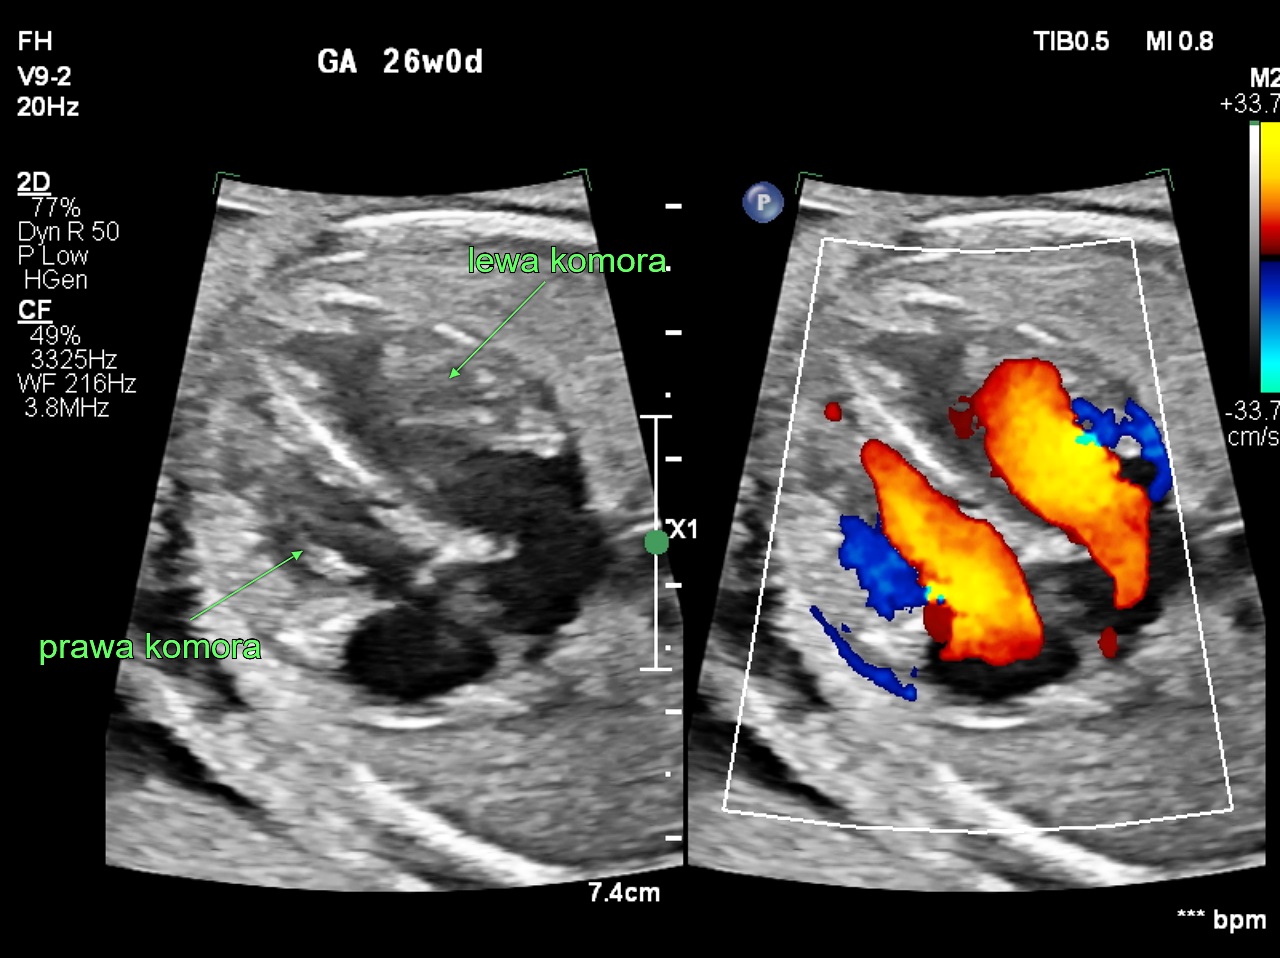

W 2011 r. kardiolodzy zajmujący się diagnostyką prenatalną w zespole prof. Joanny Szymkiewicz-Dangel oraz położnicy ze Szpitala Bielańskiego rozpoczęli pionierski w Polsce program interwencyjnej prenatalnej terapii kardiologicznej. Do zabiegów wewnątrzmacicznych kwalifikowane są płody z krytycznym zwężeniem zastawki aortalnej lub płucnej, które w innym przypadku mogłyby umrzeć lub wyniki leczenia po urodzeniu byłyby zdecydowanie gorsze.

Celem tych zabiegów jest uratowanie niedorozwiniętej lub uszkodzonej lewej lub prawej komory serca. Są to najciężej chore dzieci, którym udaje się pomóc. Zabieg poszerzenia zastawki aortalnej lub płucnej nie leczy całkowicie zastawek, ale zmniejsza nasilenie choroby i pozwala na bardziej skuteczne leczenie po urodzeniu. To dopiero pierwszy etap trudnego i długotrwałego leczenia po urodzeniu.